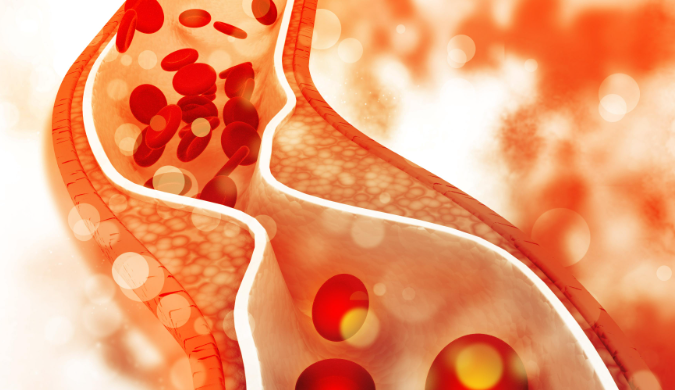

이 혈관 내부에 **죽상경화반(플라크, Plaque)**이 쌓이면 혈관 폭이 좁아지고 → 혈류량이 줄어들고 → 결국 뇌졸중으로 이어지게 됩니다.플라크는 어떻게 생길까?

플라크는 다음과 같은 물질로 구성됩니다.

- LDL 콜레스테롤

- 칼슘

- 염증 세포

- 혈관 내 손상 부위에 쌓인 지방 덩어리